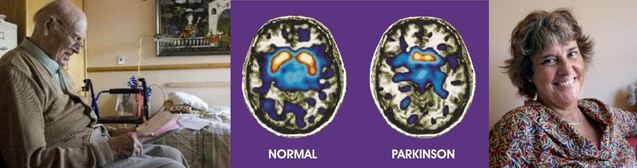

Marianne Amalric, directrice de recherche au Laboratoire de neurosciences cognitives (AMU/CNRS) et vice-présidente du comité scientifique de France Parkinson présentera ses recherches visant à améliorer les symptômes moteurs et troubles neuropsychiatriques observés chez certains malades aux stades précoces de la maladie. De nouvelles cibles thérapeutiques, comme le venin d’abeille ou les bloqueurs du glutamate, sont également expérimentées.